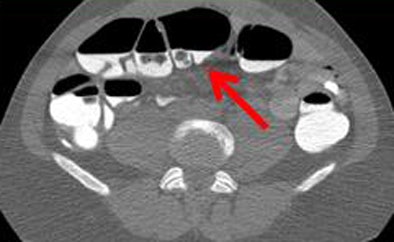

| Poor quality (1, above) means there is significant stool that is incompletely tagged; average (2, below) denotes that some incompletely tagged stool is present; and medium (3, bottom image) represents good overall quality with some stool that is not completely tagged. Superior quality (4) is generally not obtained in reduced-prep regimens. |